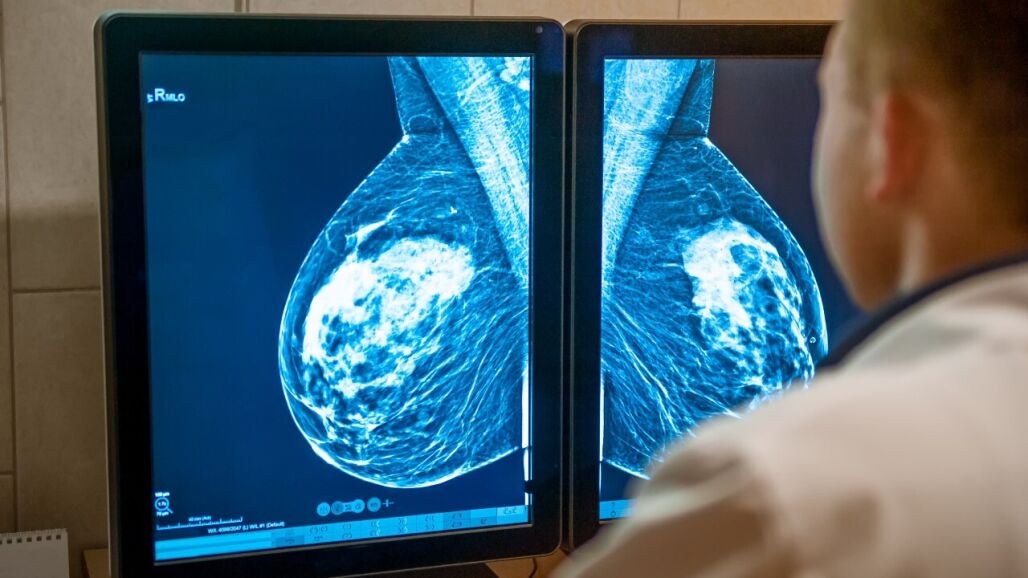

A favor, diagnósticos cada vez más rápidos y certeros, gracias a la IA. "Lo que antes se tardaba varias semanas en saber, ahora con este software de IA, tenemos el resultado en apenas treinta segundos"

Una Inteligencia Artificialque también permite acortar plazos para crear nuevos fármacos. La Fundación CRIS contra el cáncer ha creado una unidad de investigación con IA para acelerar el diseño de nuevos fármacos.